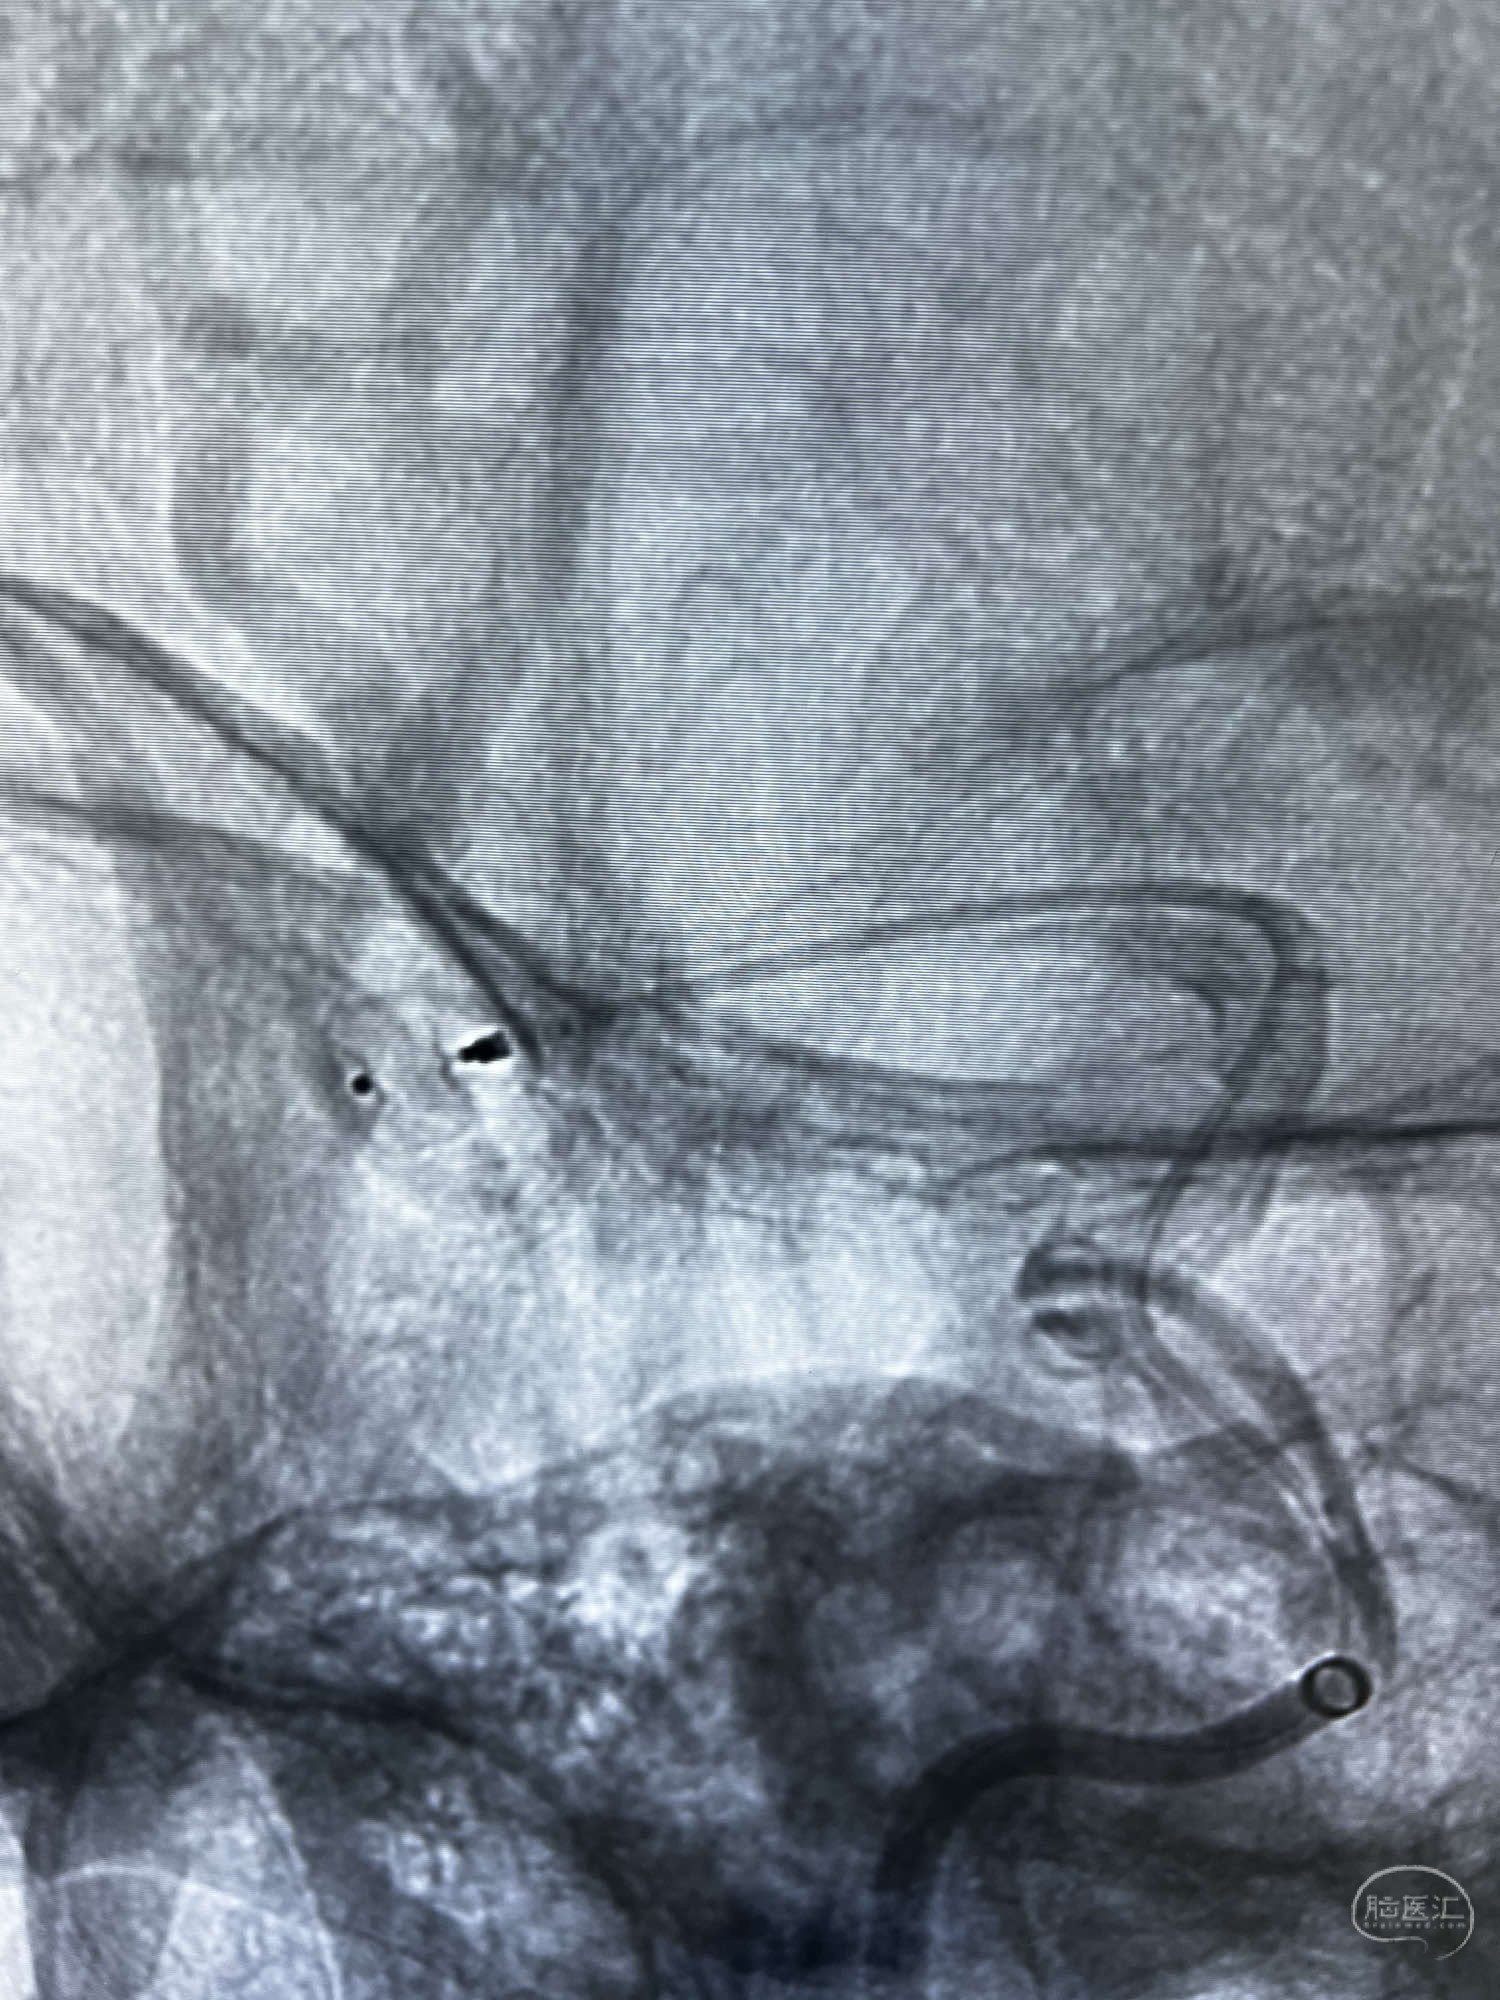

DSA示:左侧颈内动脉眼动脉段以远闭塞,后交通动脉开放,椎基底动脉通过后交通动脉代偿左侧大脑中动脉区域,右侧发出双侧大脑前动脉,右侧大脑中动脉M1末端宽颈动脉瘤,大小约4.3mmx4.6mm。

6F Neuromax➕6F115cm 心玮中间导管建立路径,sychro14微导丝➕VIA21超选至动脉瘤体内近中部,WEB5mmx3mm植入动脉瘤。